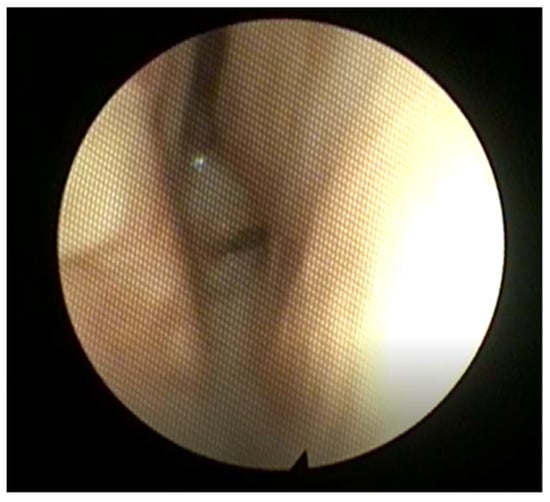

2.3. Subglottic Stenosis